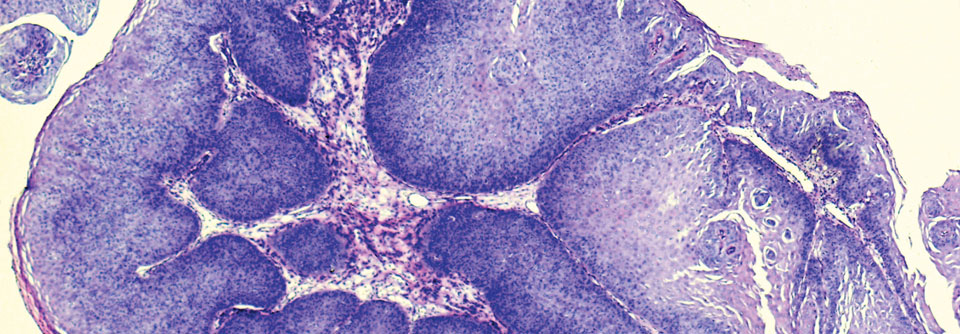

Die prophylaktische Impfung gegen humane Papillomviren (HPV) kann verschiedene Karzinome und Krebsvorstufen sowie Genitalwarzen verhindern. Doch die…